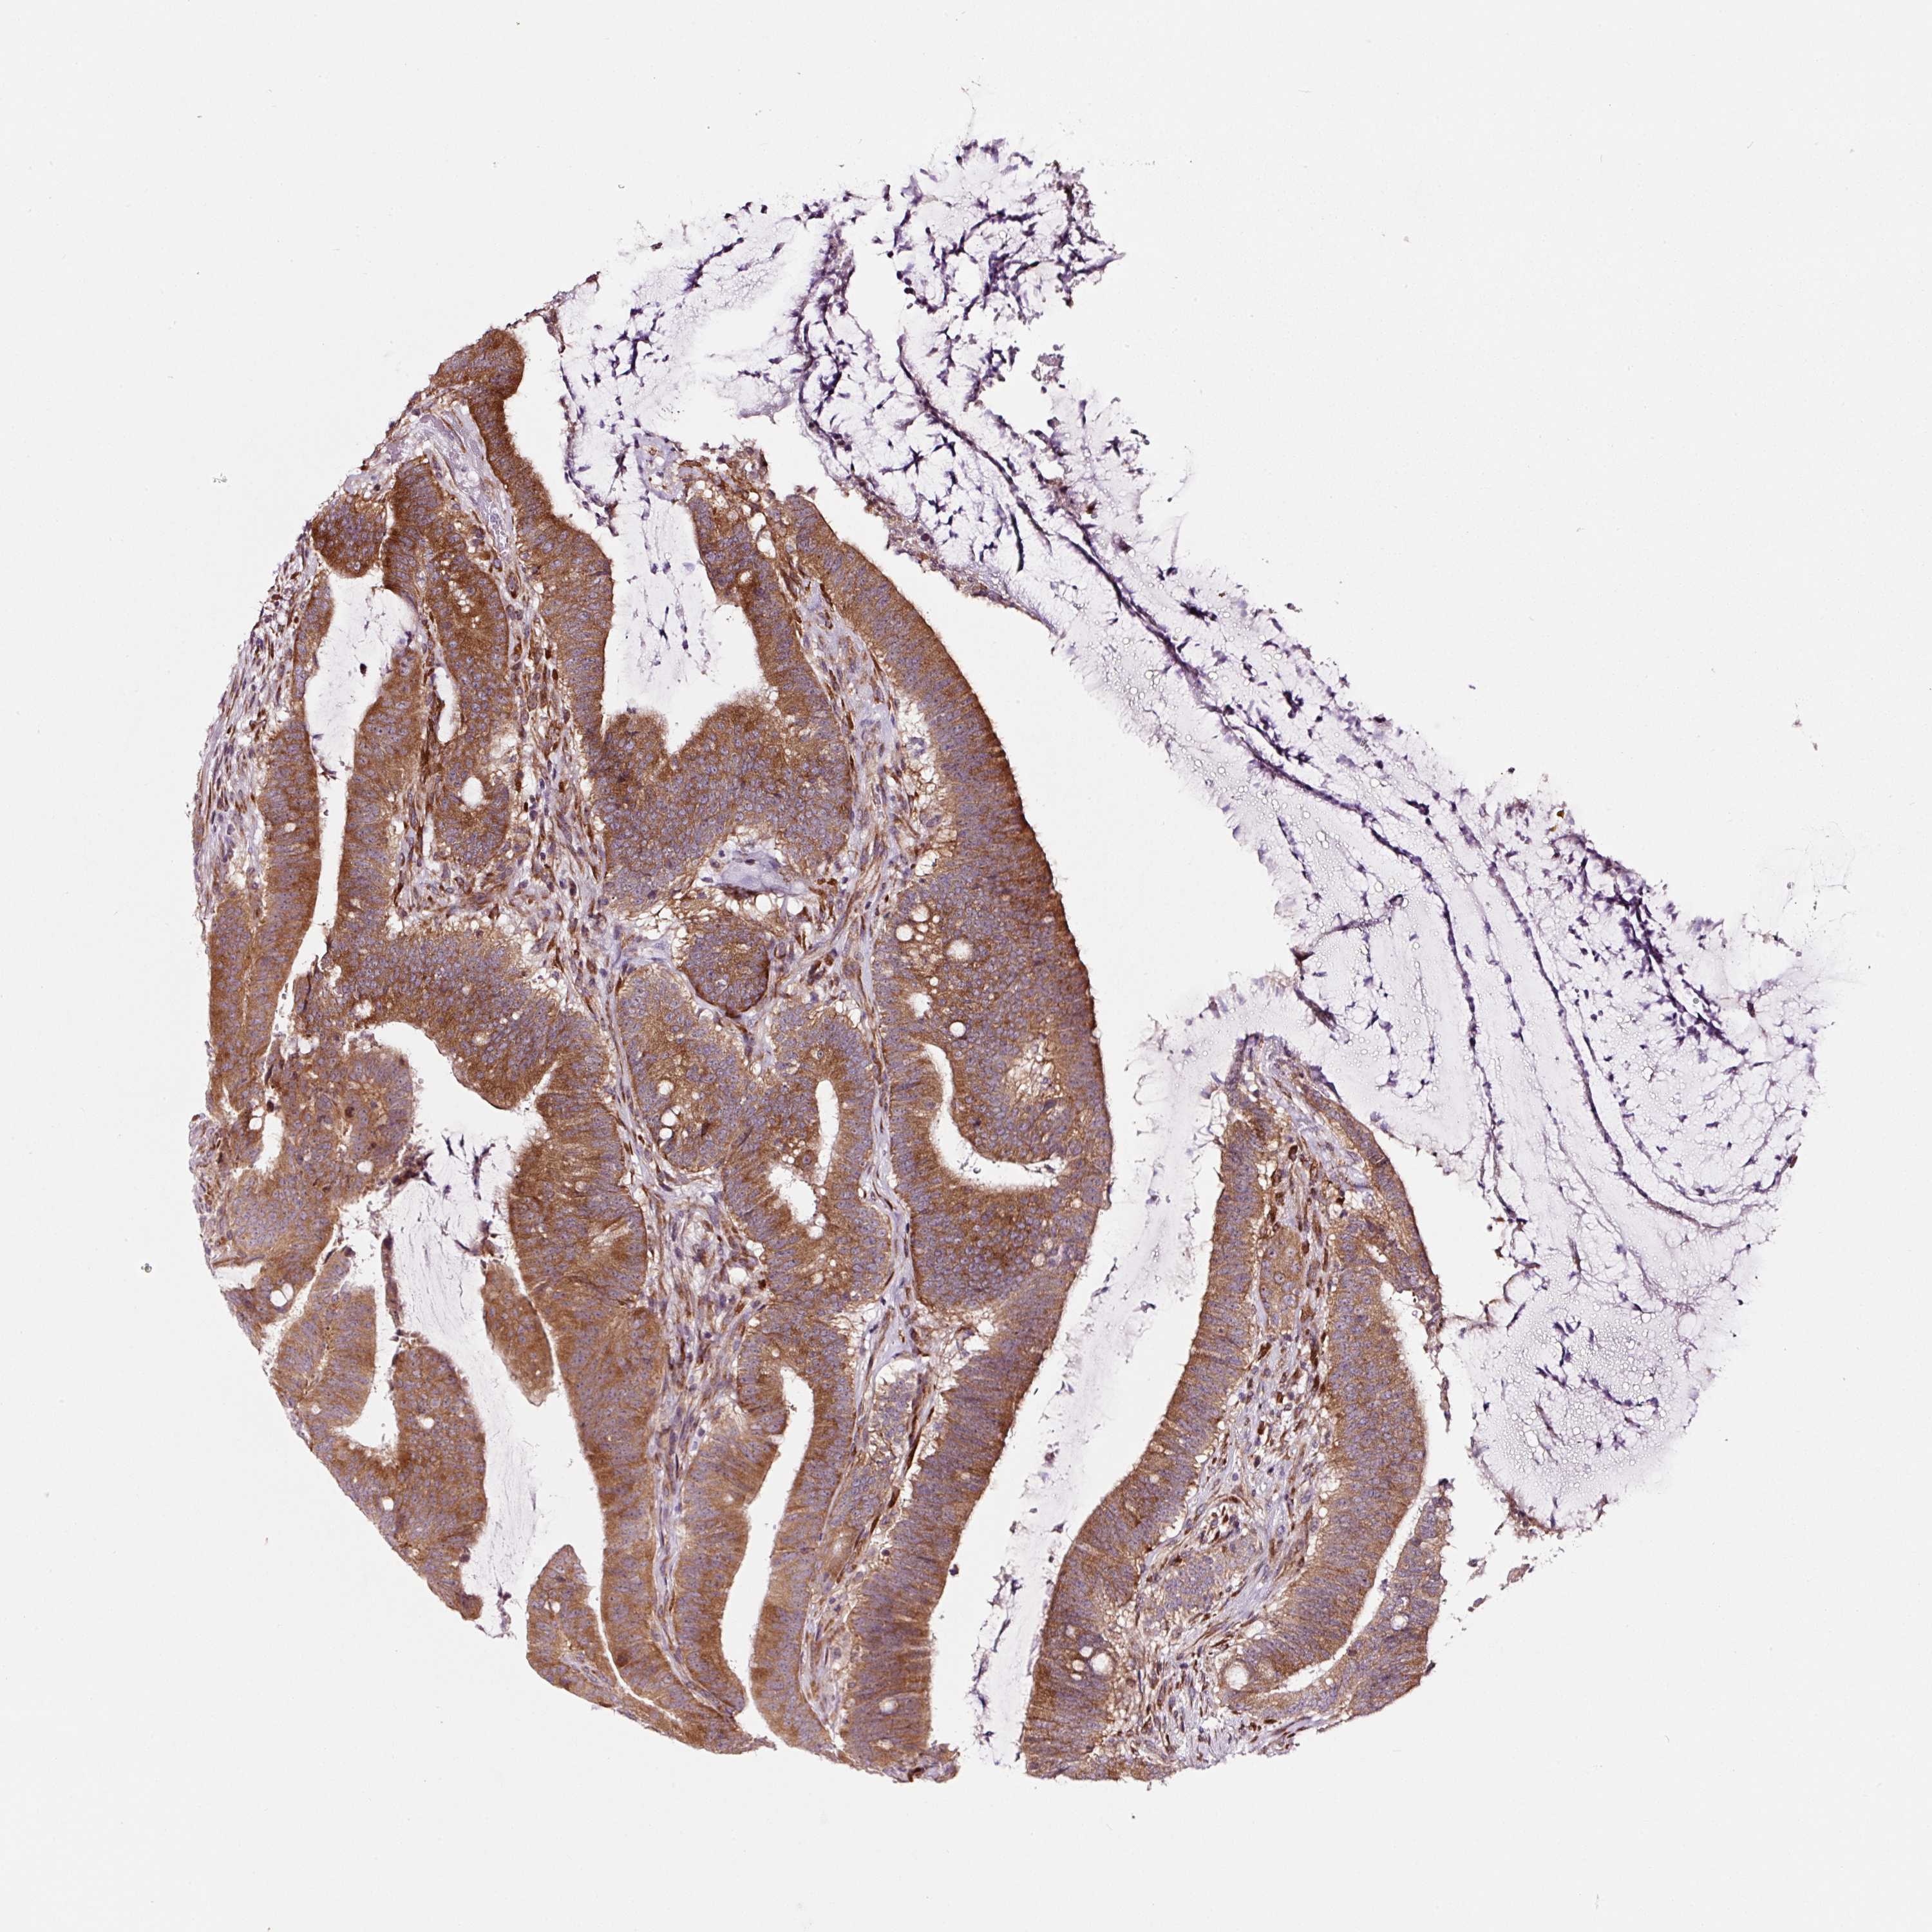

CANCER COLORECTAL CANCER Show tissue menu

Colorectal cancer

Human cancer

Colon adenocarcinoma

Rectum adenocarcinoma